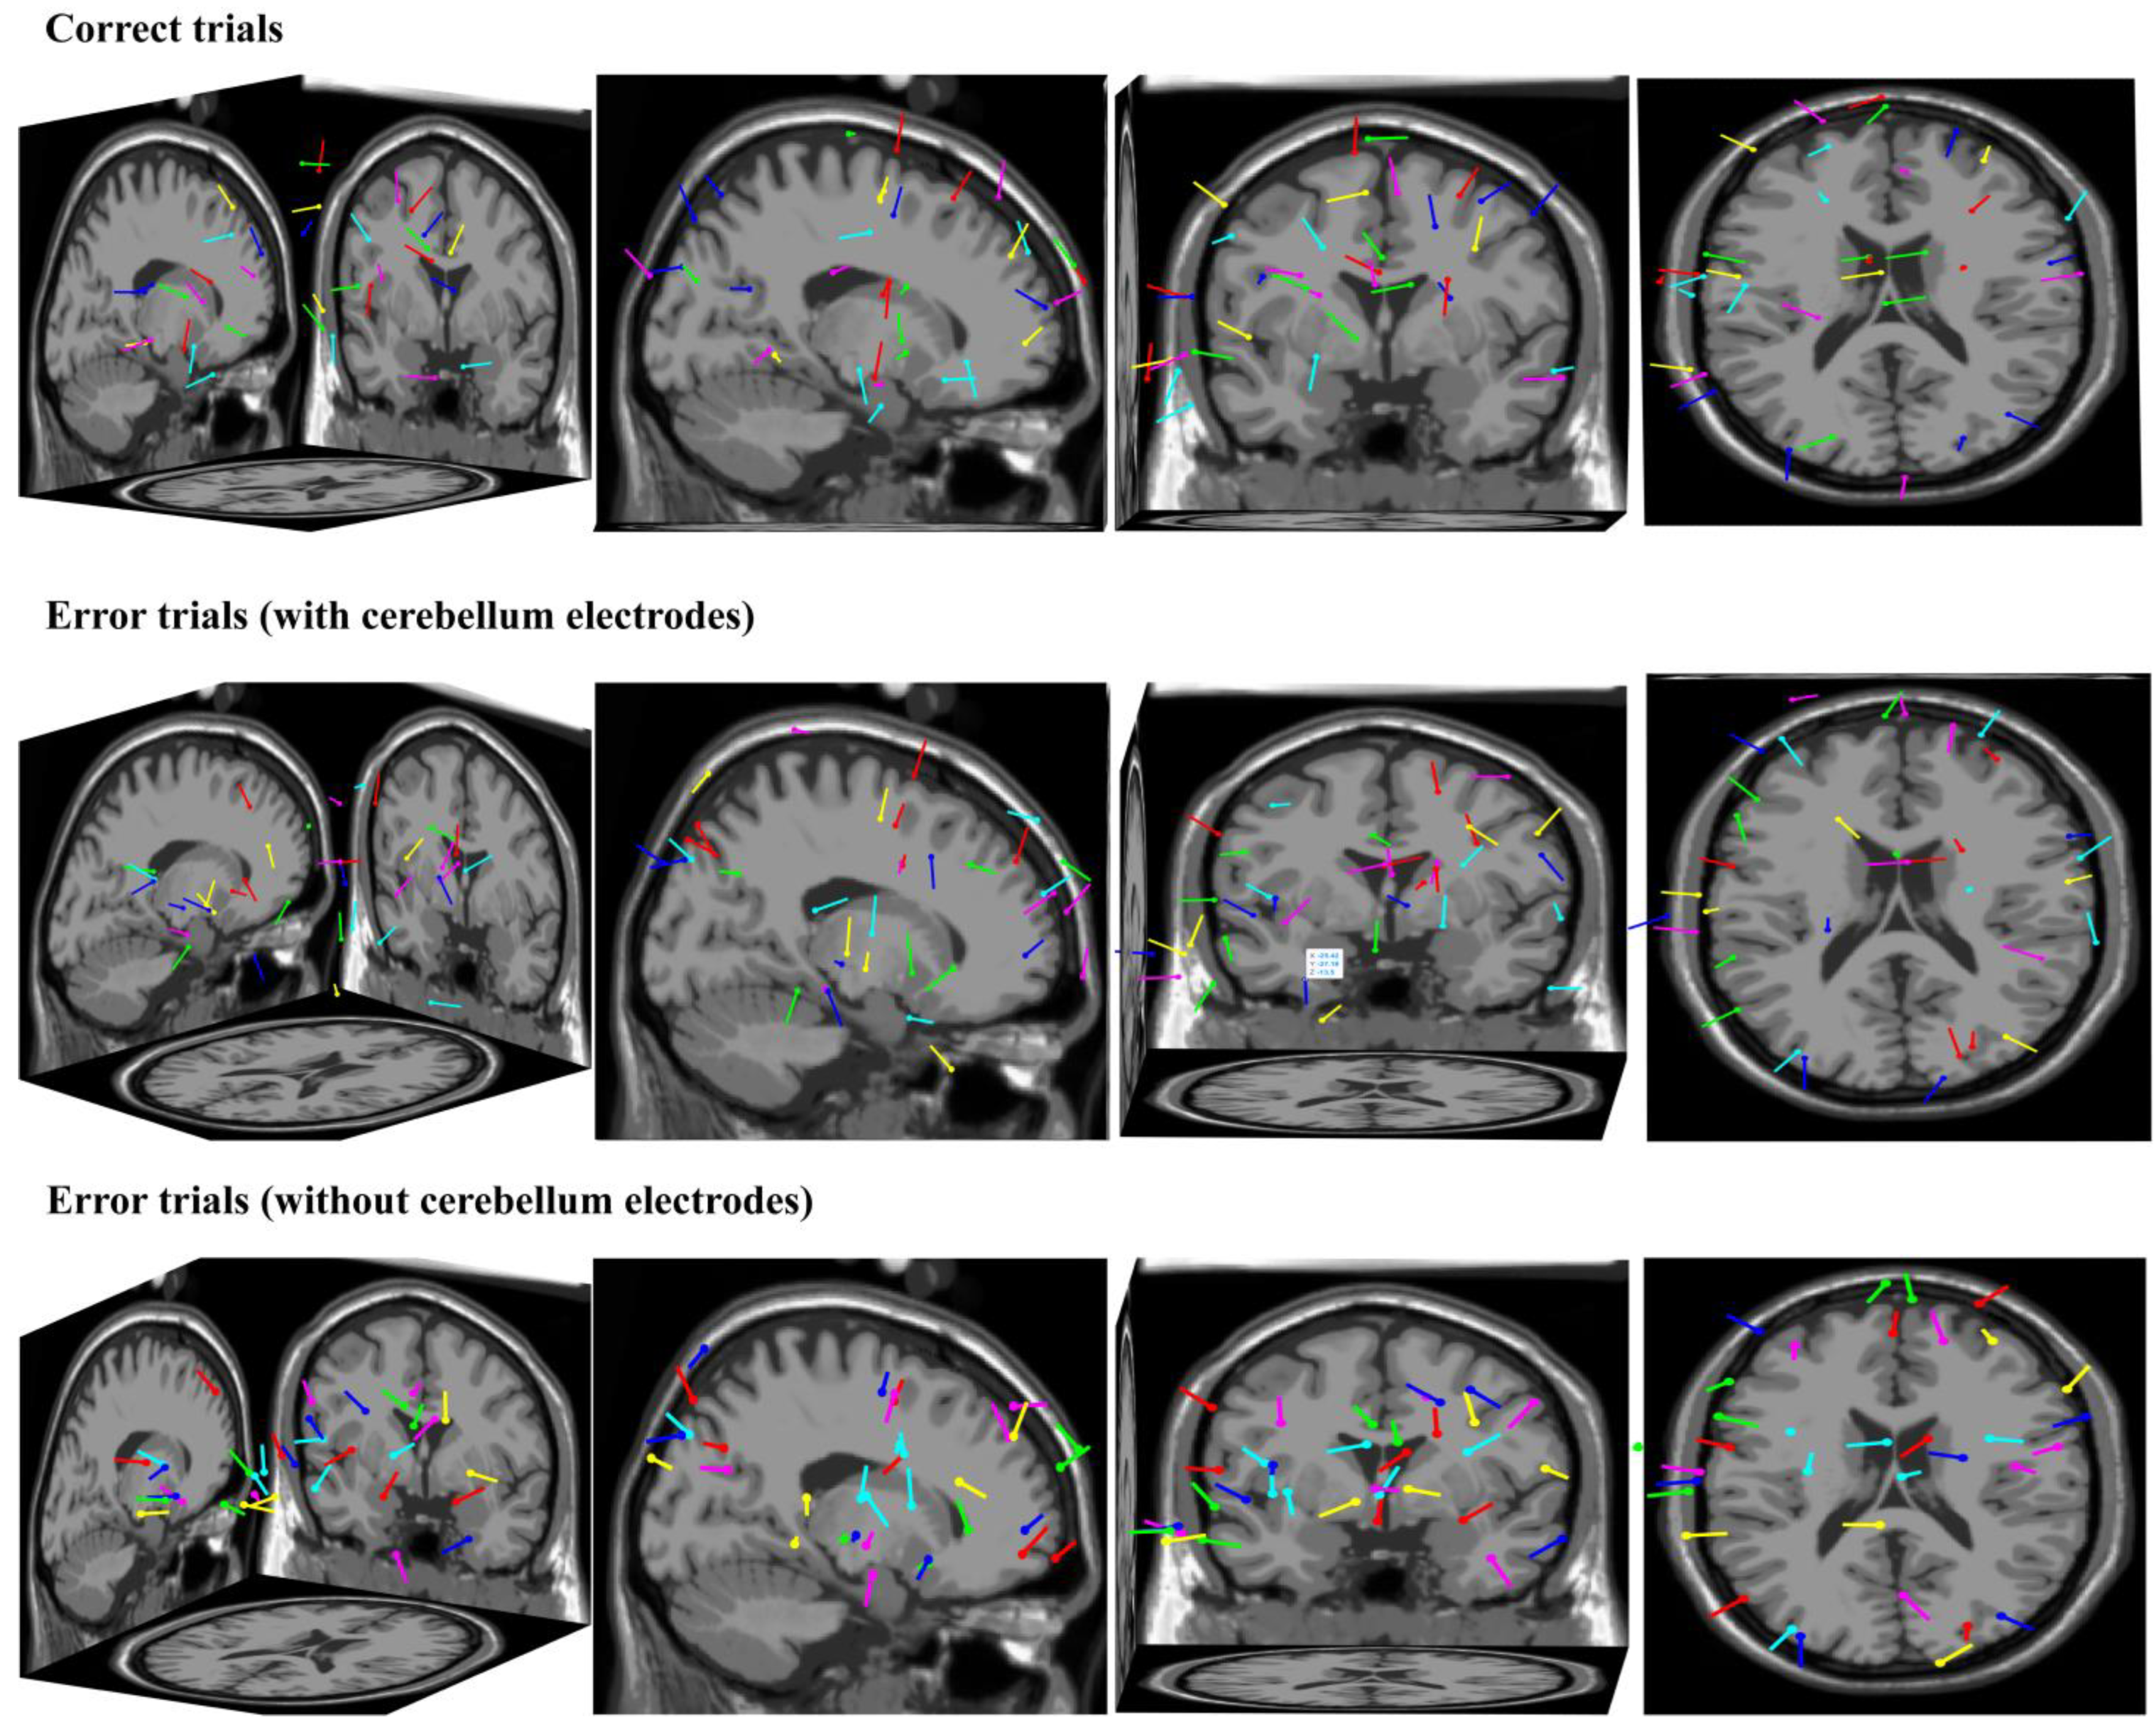

From the perspective of the source analysis, we used ICA and Dipfit to perform dipole localization analysis on the dataset collected in this study. The data-processing steps were as follows: (1) we took the button press moment of the participant as time zero and we extracted the EEG data from −200 ms to 500 ms for a single trial; (2) trials that went overtime or had obvious artifact interference were excluded; (3) the remaining trials were divided into correct and error trials, which were then subjected to independent component analysis and dipole localization, respectively, yielding the localization results shown in Figure 8. The first row shows the dipole localization results for correct trials from different perspectives, while the second row and third row show the dipole localization results for error trials with and without cerebellum electrodes, respectively. It can be observed that in the dipole localization results for error trials with cerebellum electrodes, there was a certain degree of activation in the cerebellar region (dipole 1—X: −59, Y: −39, Z: −13; dipole 2—X: −25, Y: −27, Z: −13), which was not present in the dipole localization results for correct trials and error trials without cerebellum electrodes. This further illustrates the representation of cerebellar activity at the neck scalp electrodes during error-related potential activation.

Figure 8. The dipole localization results for correct and error trials.

Brainsci 14 00214 g008